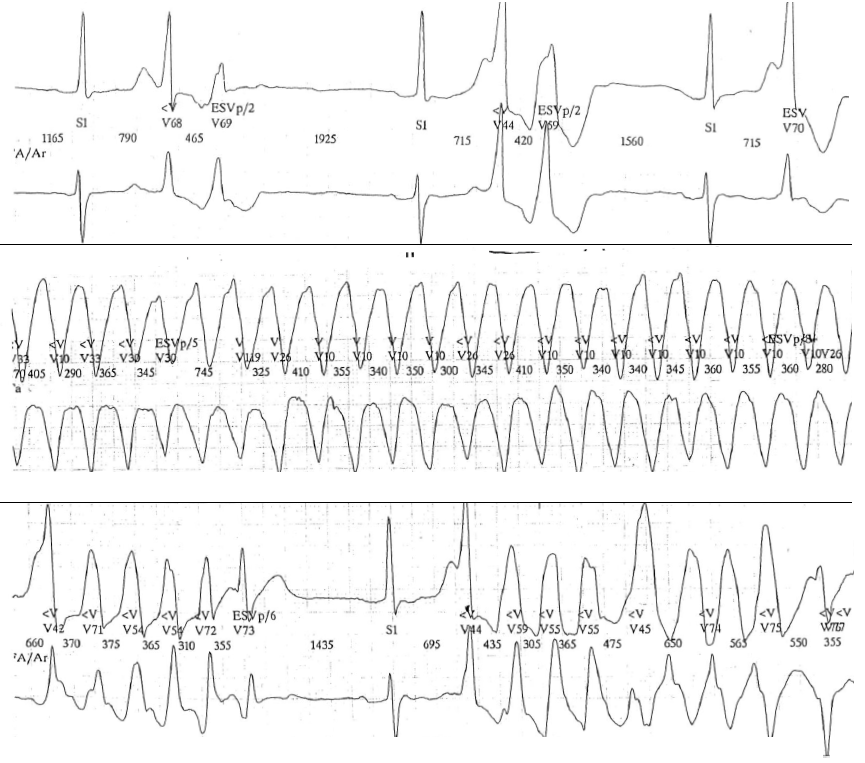

2) un facteur déclenchant: l’épisode de tachycardie est annoncé et déclenché par la survenue d’extrasystoles ventriculaires pas forcément très précoces mais tombant sur l’onde T du complexe précédent du fait de son allongement marqué. L’apparition d’un bigéminisme ventriculaire chez un patient avec intervalle QT prolongé doit faire redouter la survenue d’une torsade de pointes, l’allongement de la diastole liée à la pause post-extrasystolique prolongeant la repolarisation du complexe conduit. De même, l’alternance de l’onde T ou de l’onde U est un signe électrocardiographique précurseur de torsade. Ces extrasystoles sont généralement en rapport avec la survenue de post-dépolarisations précoces.

3) un aspect de tachycardie très évocateur: la tachycardie est rapide et polymorphe, marquée par la succession rapide (en général entre 50 et 250 bpm) de complexes ectopiques ventriculaires larges, de polarité variable avec rotation progressive et cyclique autour de la ligne isoélectrique. La repolarisation reste généralement identifiable, la différenciation des complexes QRS et ondes T étant le plus souvent possible ce qui diffère d’un tracé de fibrillation ventriculaire (impossibilité d’identifier complexes QRS et ondes T). Une torsion autour de la ligne de base est à l’origine du terme de torsades de pointes, le sens des “pointes” s’inversant brutalement tous les 5 à 10 complexes (ou plus) parfois à l’occasion d’un bref ralentissement de fréquence. L’aspect caractéristique d’ondulation du tracé peut n’apparaitre que dans certaines dérivations, l’enregistrement simultané de plusieurs dérivations (notamment les dérivations frontales) étant nécessaire pour mettre en évidence l’aspect hélicoïdal du tracé. Les ondes P sont dissociées mais ne sont pas visibles.

4) des épisodes spontanément résolutifs: les torsades de pointes surviennent généralement par accès de quelques secondes à quelques dizaines de seconde se réduisant spontanément. La cessation spontanée et souvent brutale de l’accès après une courte pause ventriculaire est caractéristique de cette forme d’arythmie, ce qui explique la survenue fréquente d’une syncope (retour spontané à la conscience) plutôt qu’une mort subite. Il existe une tendance marquée à la récidive et certains accès prolongés peuvent finir par dégénérer en fibrillation ventriculaire.